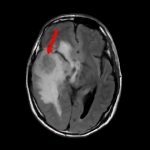

断層撮影

手術前1

手術前2